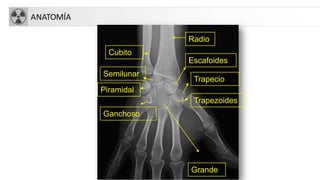

ANATOMÍA

Trapezoides

Radio

Cubito

Escafoides

Semilunar

Piramidal

Trapecio

Grande

Ganchoso